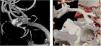

Cerebral digital subtraction angiography (DSA) remains the gold standard for the control of aneurysmal remnants after surgical clipping. Despite being associated with minimal risks, it is an invasive procedure far from being iatrogenia free. Furthermore, it has limited availability which may prolong patient’s postoperative stay. On the other hand, the image quality of computed tomography angiography (CTA) has improved significantly over the past decades providing a valuable alternative to DSA. The objective of this study was to compare the capacity of CTA and DSA to detect clinically significant aneurysmal remnants.

From a prospective series of surgically treated aneurysms, those with postoperative CTA and DSA were retrospectively included in the study. A three-dimensional reconstruction of the CTA was performed using the Brainlab Elements software and the results were compared with those of the DSA. In addition, variables that could affect the three-dimensional reconstruction were collected, such as the number of clips per aneurysm and previous clipping or embolization. In case of an aneurysm remnant, its size was also recorded.

Between January 2020 and January 2022, a total of 42 patients in whom 52 aneurysms were clipped (8 of them ruptured) were included. CTA presented a sensitivity of 50% and a specificity of 97% in the detection of aneurysmal remnants. The cases in which CTA did not detect the aneurysmal remnant were previously embolized aneurysms or complex aneurysms that required neck reconstruction with 3 or more clips. None of the remnants undetected by CTA were significant enough to warrant retreatment of the aneurysm.

Excluding complex aneurysms (previously embolized or requiring surgical reconstruction with 3 or more clips), three-dimensional reconstructions of CTA images showed excellent results in detecting clinically significant postoperative aneurysm remnants and may obviate the need for a the more invasive and less available DSA.